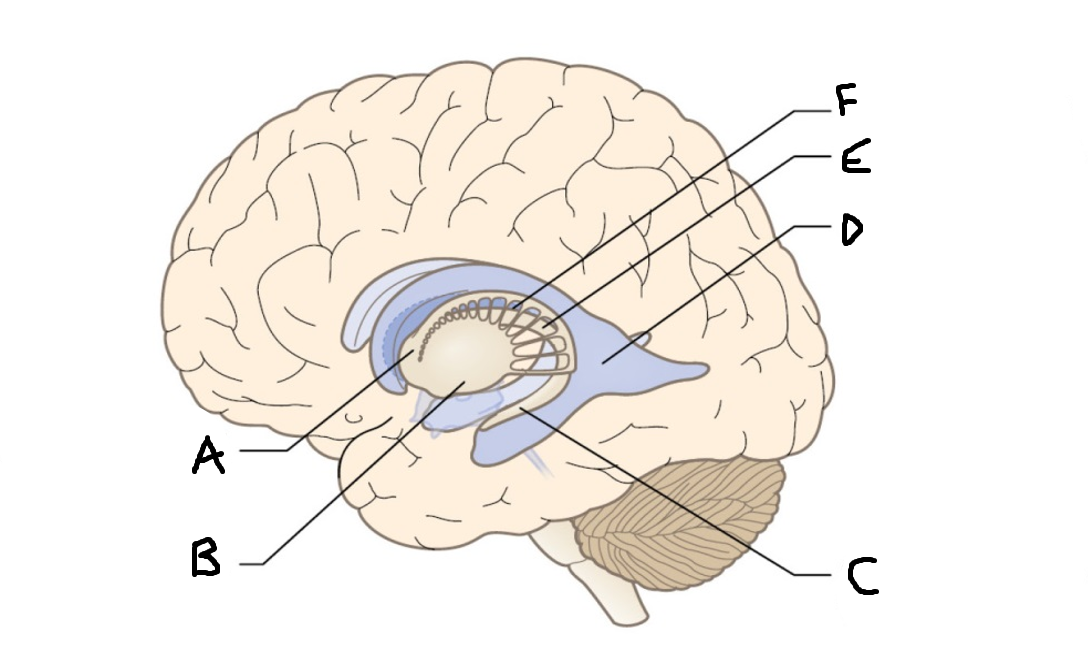

A

head of caudate nucleus

C

putamen

D

external segment of globus pallidus

E

internal segment of globus pallidus

F

third ventricle

G

thalamus